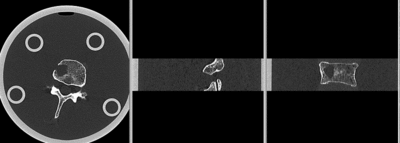

• the baseline container contains the vertebra upside down (as apparent from orientation of the pedicle/roots of the vertibral arches coming out of the body, visible in sagittal or coronal view). Hence this image needs to have its z-axis (IS) reversed before registration

• the containers walls and lid contain dominant image content that would prevent a successful automated registration; cropping is required

• the two vertebrae have strong rotational misalignment; manual initial alignment is recommended

original unregistered unregistered

registered (after flipping axis and cropping volume) registered